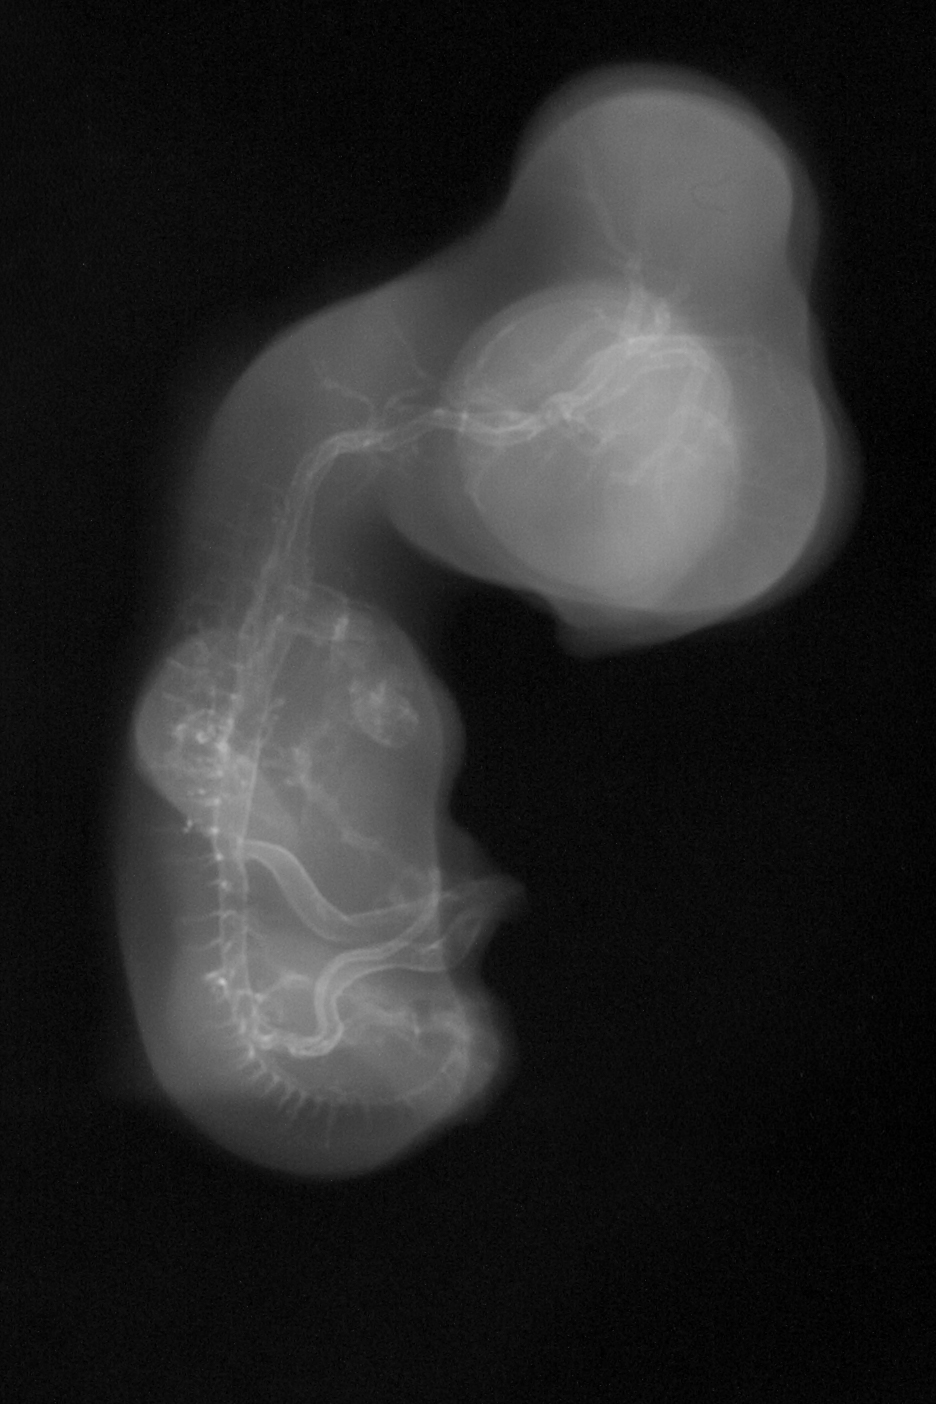

Chick Embryo Microangiography

Hamburger-Hamilton (HH) Stage 29 (approx. 6 - 6.5 days)

Stereo X-Ray Micrographs